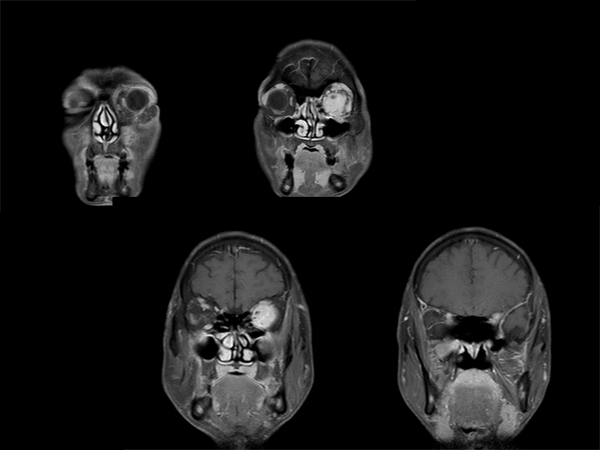

診断:下垂体炎、硬膜炎、三叉神経の炎症性偽腫瘍

【画像所見】

眼瞼腫脹と視力低下

見るからに眼窩内偽腫瘍 + 三叉神経の腫大

造影後冠状断

下垂体炎、硬膜炎、三叉神経の炎症性偽腫瘍